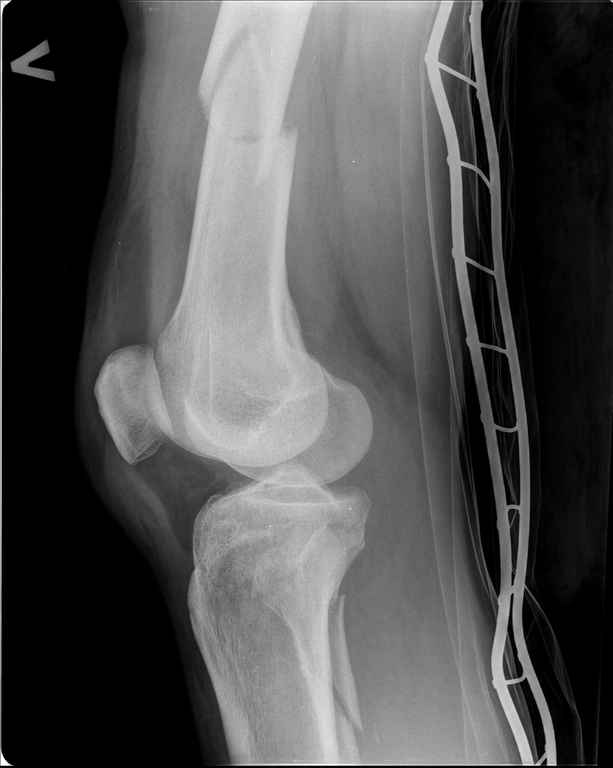

состоянии. Ds: ТСТ. ЗЧМТ. СГМ. ЗТГК. О/фрагментарный перелом левого бедра. З/оскольчатый

перелом с\3 левого плеча. Перелом левого локтевого отростка. З/перелом наружного мыщелка

б/берцовой кости в/3 м/берцовой кости левой голени. при поступлении, ПХО раны левого бедра(

версия Fi-Can Sanatmetal диаметр 10мм), мыщелок голени трогать не стали.при остеосинтезе